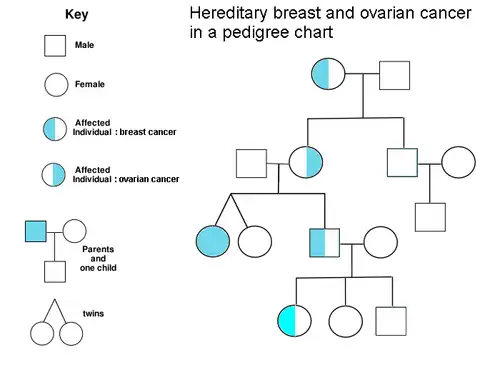

Genetics

A family history of ovarian cancer is a risk factor for ovarian cancer. Women with hereditary nonpolyposis colon cancer (Lynch syndrome), and those with BRCA-1 and BRCA-2 genetic abnormalities are at increased risk.

The major genetic risk factor for ovarian cancer is a mutation in BRCA1 or BRCA2 genes, or in DNA mismatch repair genes, which is present in 10% of ovarian cancer cases. Only one allele needs to be mutated to place a person at high risk. The gene can be inherited through either the maternal or paternal line, but has variable penetrance.[26][29] Though mutations in these genes are usually associated with increased risk of breast cancer, they also carry a substantial lifetime risk of ovarian cancer, a risk that peaks in a person's 40s and 50s. The lowest risk cited is 30% and the highest 60%.[28][26][29] Mutations in BRCA1 have a lifetime risk of developing ovarian cancer of 15–45%.[31] Mutations in BRCA2 are less risky than those with BRCA1, with a lifetime risk of 10% (lowest risk cited) to 40% (highest risk cited).[26][31] On average, BRCA-associated cancers develop 15 years before their sporadic counterparts because people who inherit the mutations on one copy of their gene only need one mutation to start the process of carcinogenesis, whereas people with two normal genes would need to acquire two mutations.[29]

In the United States, five of 100 women with a first-degree relative with ovarian cancer will eventually get ovarian cancer themselves, placing those with affected family members at triple the risk of women with unaffected family members. Seven of 100 women with two or more relatives with ovarian cancer will eventually get ovarian cancer.[29][38] In general, 5–10% of ovarian cancer cases have a genetic cause.[29] BRCA mutations are associated with high-grade serous nonmucinous epithelial ovarian cancer.[31]

A strong family history of endometrial cancer, colon cancer, or other gastrointestinal cancers may indicate the presence of a syndrome known as hereditary nonpolyposis colorectal cancer (also known as Lynch syndrome), which confers a higher risk for developing a number of cancers, including ovarian cancer. Lynch syndrome is caused by mutations in mismatch repair genes, including MSH2, MLH1, MLH6, PMS1, and PMS2.[26] The risk of ovarian cancer for an individual with Lynch syndrome is between 10 and 12 percent.[26][29] Women of Icelandic descent, European Jewish descent/Ashkenazi Jewish descent, and Hungarian descent are at higher risk for epithelial ovarian cancer.[29] Estrogen receptor beta gene (ESR2) seems to be a key to pathogenesis and response to therapy.[39] Other genes that have been associated with ovarian cancer are BRIP1, MSH6, RAD51C and RAD51D.[40] CDH1, CHEK2, PALB2 and RAD50 have also been associated with ovarian cancer.[41]